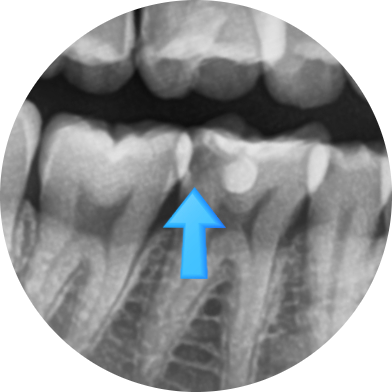

x-ray를 통해 충치가 있다고 진단받은 치아 6개월 후 파절되어 오심

결국 6개월 후에는 치아가 깨졌다며 오셨습니다.

치아 대부분이 무른 충치이고, 단단한 부분은 껍질처럼 얇게 남아있었기 때문에 치아가 쉽게 깨지게 됩니다.

물론 신경치료+크라운을 시도해보겠지만

결국 오셨을 때는 치아가 예전보다 너무 많이 파절되어 크라운도 하기 힘들 수도 있습니다.

발치 가능성이 예전보다 더 높아진 상태로 오셨습니다.